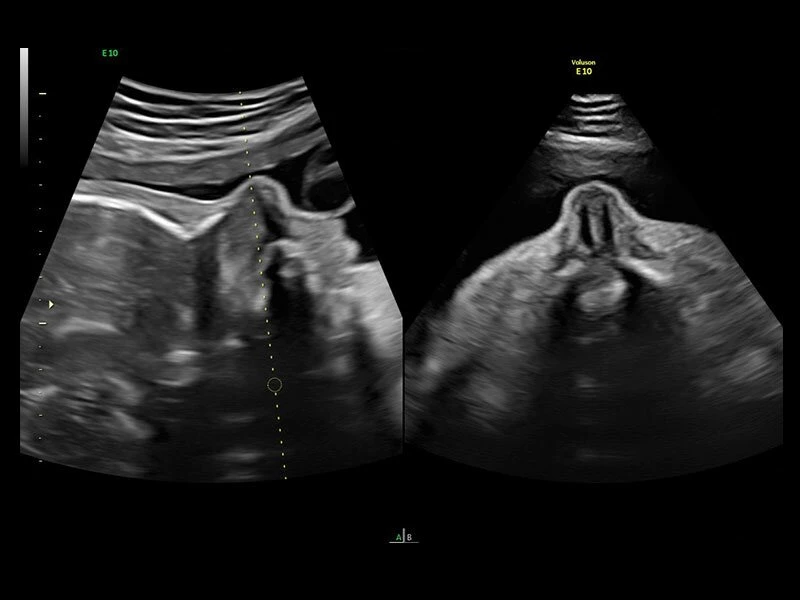

Voluson E10 – премиум класс среди ультразвуковых диагностических аппаратов для акушерских, гинекологических и объемных исследований. Аналогов системе Voluson E10 на рынке не представлено. УЗИ аппарат Voluson E10 обладает возможностью подключения электронного матричного датчика с количеством элементов не менее 8000.

Ультразвуковой аппарат идеально подходит для акушерско- гинекологических исследований. Гарантирует точное и четкое изображение.

Система обеспечивает инновационную четкость при работе. Новая платформа Radiance System Architecture системы разработана для превосходной визуализации как в стандартных режимах, так и при 3D/4D-визуализации.

Четкие и подробные изображения

В медицинском учреждении, которое работает в условиях высокой нагрузки, значение имеет каждая минута. У врача нет времени подолгу корректировать параметры настройки, чтобы добиться наилучшей детализации изображения. Инновационная архитектура УЗИ аппарата Voluson E10 избавляет вас от лишних хлопот, — вы сразу получаете безукоризненную картинку. Вам не придется тратить лишнее время и силы: качество визуализации безупречно в любом режиме — от двумерных изображений до новейших 3D/4D технологий.

Современные клинические приложения и высокое качество изображений позволяют использовать Voluson E10 для наблюдения за ходом беременности максимально эффективно. С помощью этого аппарата можно проводить любые исследования, как рутинные, так и комплексные, выявляя проблемы на ранних стадиях и принимая своевременные меры.